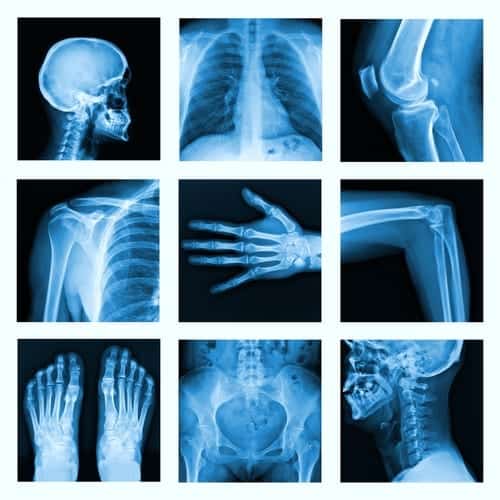

Collage of many X-rays in very good quality.Taking care of yourself is a very important part of being and staying healthy. Of course, there are many different temptations that face us all the time. While there’s nothing wrong with indulging a sweet tooth every now and then, or in having a glass of wine to relax after a long hard day, it’s important to know what you have to do in order to be healthy for the long run.

When you are healthy, it means that you are able to do all of the things you want to do without fear that your body is going to fail you. Being healthy means that you can live a life that is unencumbered by soreness, joint pain or health problems. Working to stay healthy can get more difficult as we age, but there are plenty of people who manage to stay healthy and are all the better for it. A key component of health as you age is bone health; our bones are what make up our skeleton. So it is important to ensure you have a strong and healthy skeletal system. Bone loss is one of the key factors that is responsible for a weakened skeleton, so let’s take a look at the top five factors that contribute to bone loss.